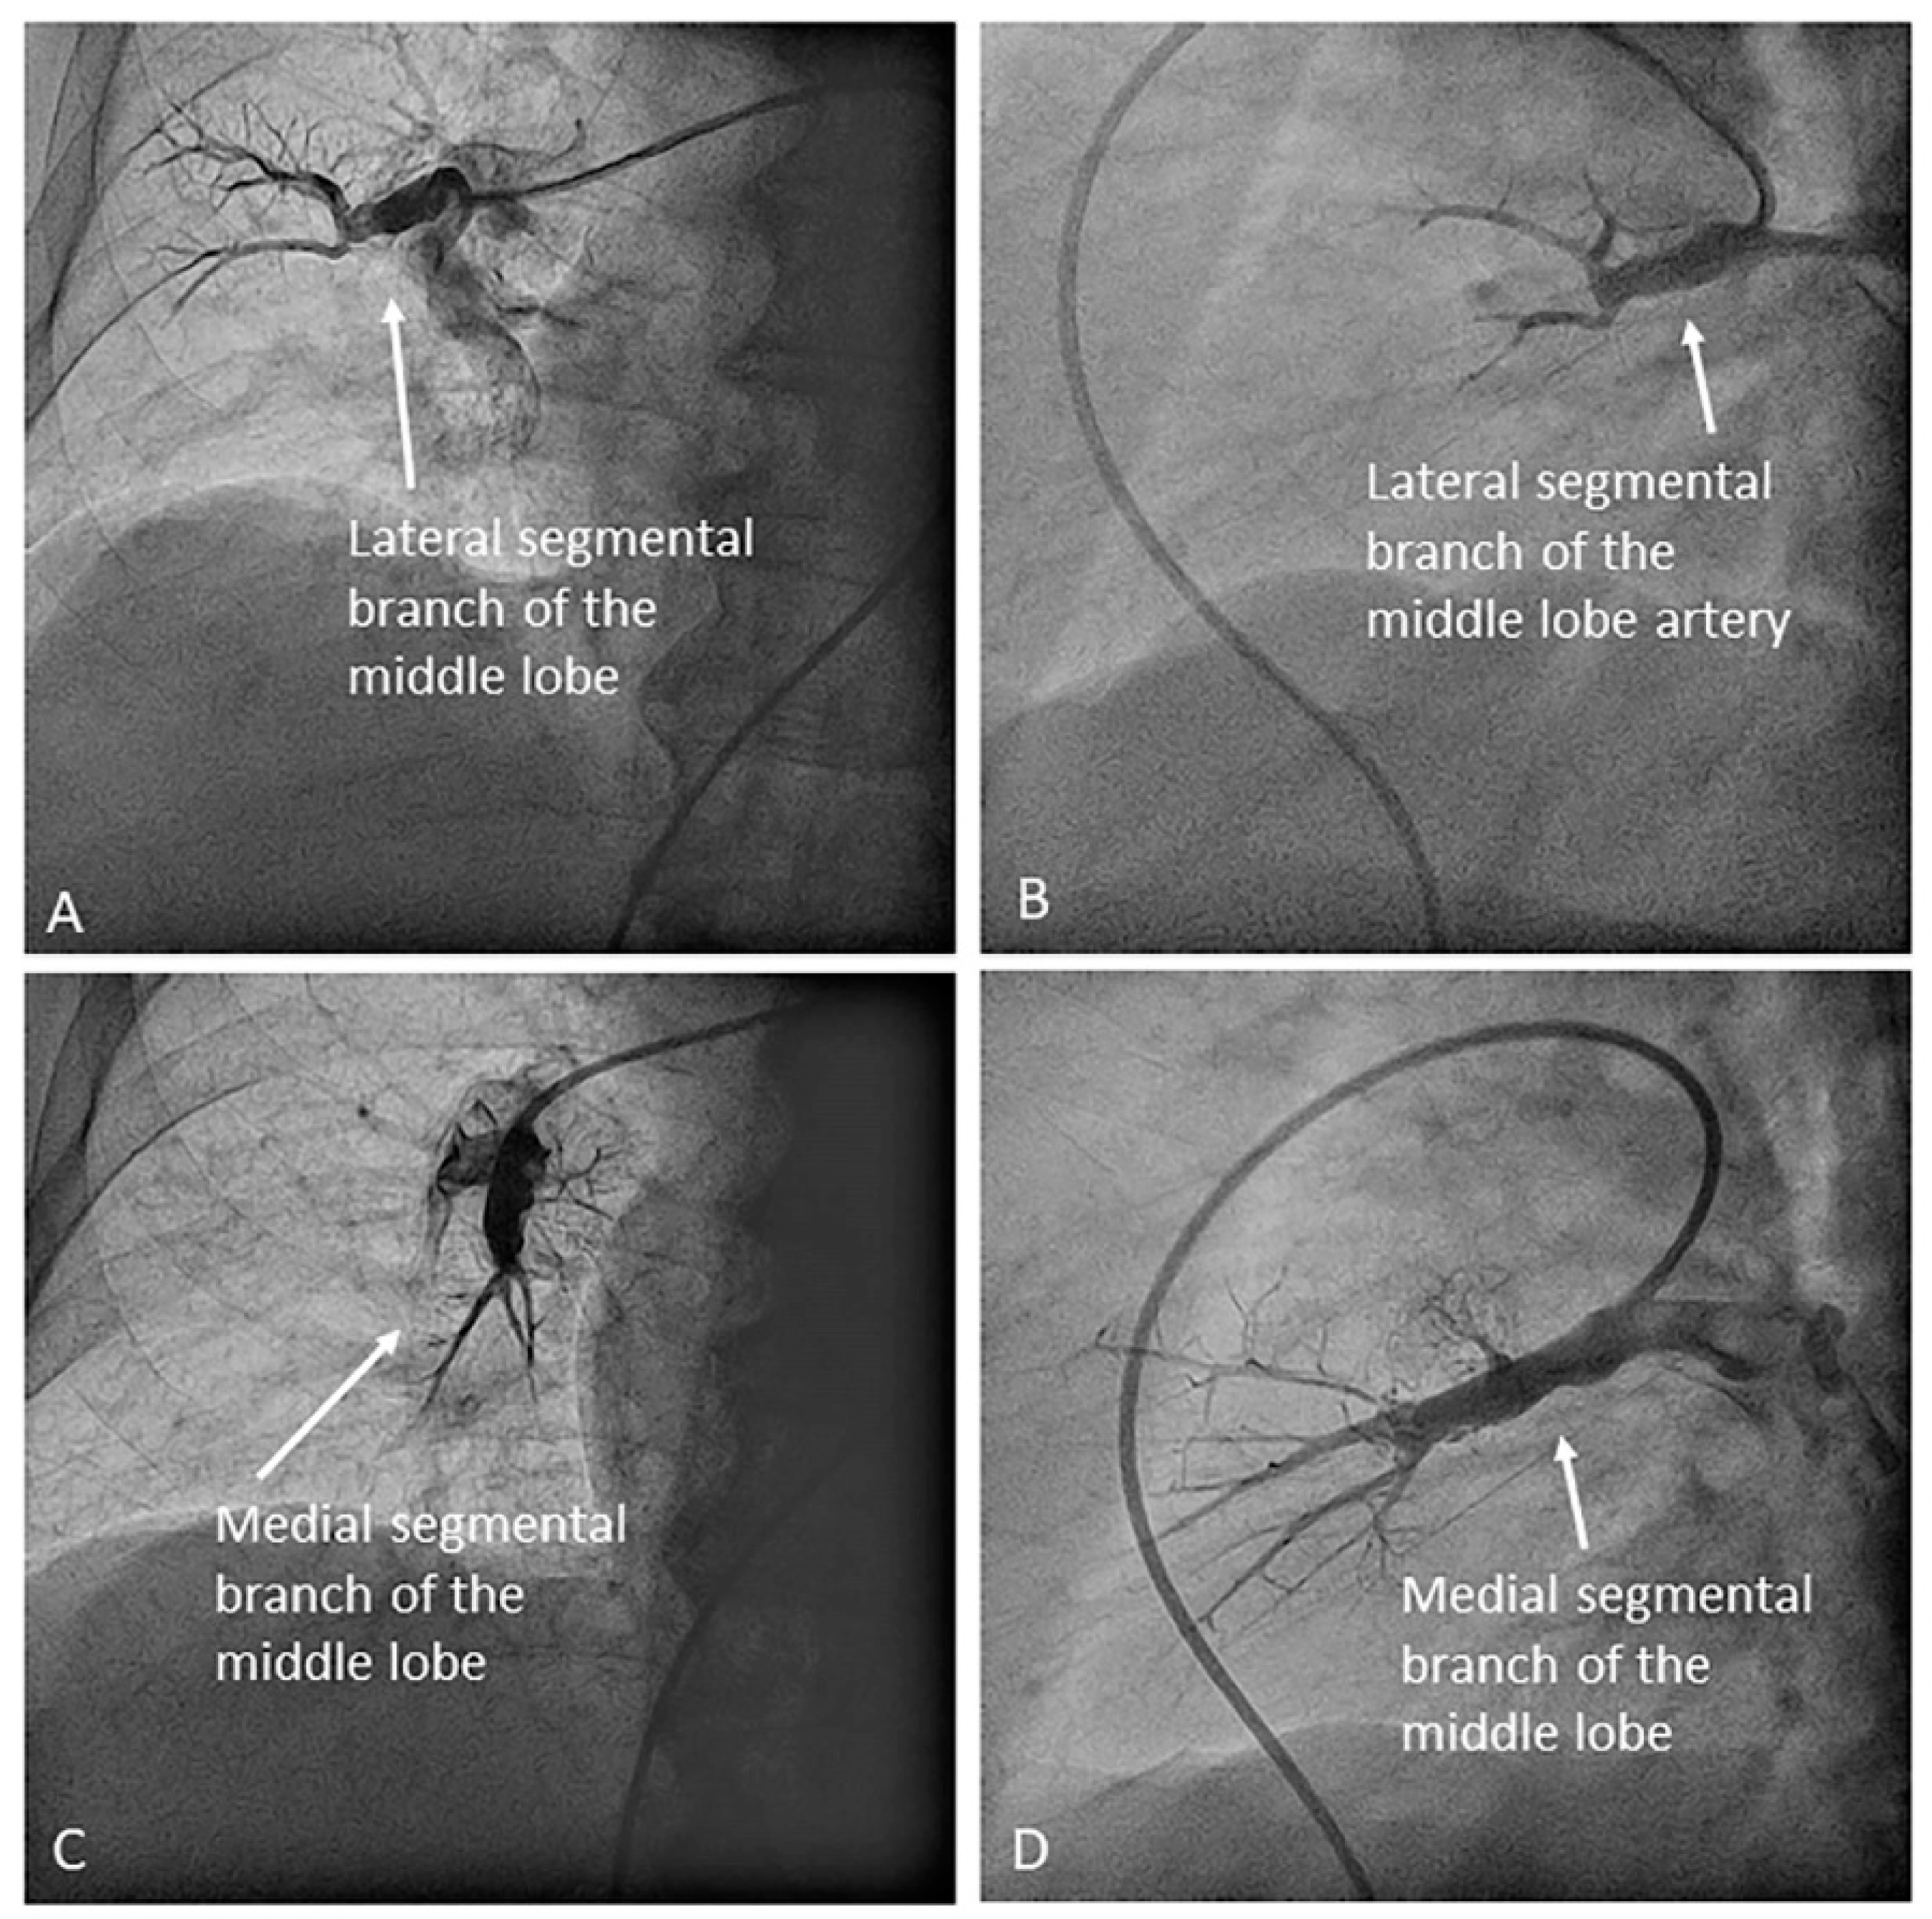

- Middle lobe. The middle lobe artery originates in front of the superior segmental artery of the RLL (A6), with an anterior direction, as does the lingula in the left lung (Figure 14). It is canalized with the MP, in the lateral view. The distal angulated segment of the MP should be bent, pressing against the bifurcation of the RLL, and rotated counterclockwise, with the tip of the catheter pointing towards the sternum (Figure 30). The JR 4 is also a good alternative. This artery bifurcates early in two segmental branches: lateral (A4) and medial (A5). The lateral and cranial LAO views display both branches. If these segmental branches have an independent origin in the RPA, they should be cannulated and filmed independently (Figure 31).